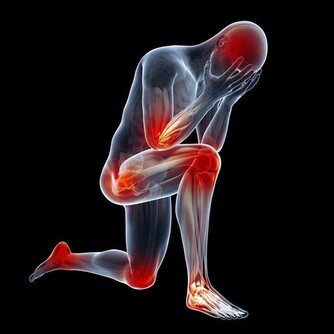

*****2.酸脹不適:*****

腿部覺得沉重、乏力、瘙癢,更甚者會出現脹痛不適,

這些症狀在睡了一天以後會明顯緩解,而在長時間站立或行走後明顯加重。

*****3.明顯腫脹:*****

一側腿部明顯腫脹。

肢體發冷或肢體潮熱,靜脈曲張患者患肢變細,變粗皮膚有針刺感、奇癢感、麻木感、灼熱感等。